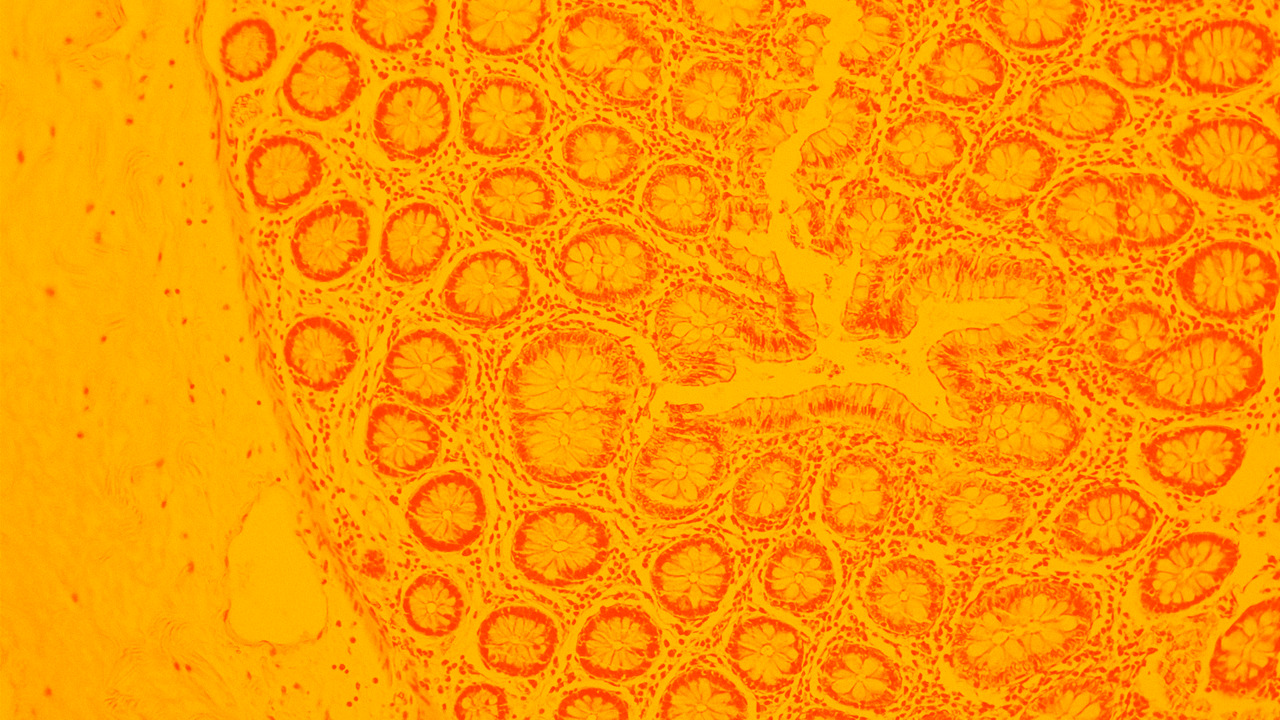

Kort- och långsiktiga behandlingsmål, med definierade kliniska endpoints: Det är av största vikt för en framgångsrik behandling enligt James Lindsay, professor i inflammatorisk tarmsjukdom och överläkare i gastroenterologi. Ta del av hans föreläsning där viktiga biomarkörer och insikter kring bland annat prevention och fördelarna med biologiska läkemedel delas.

Anmäl dig härProfessor Laurent Peyrin-Biroulet höll en föreläsning om IBD och olika behandlingsstrategier med fokus på IL-23 hämmare.

Hur ser morgondagens terapier och behandlingsmål för IBD ut? Torsten Kucharzik, professor och överläkare i gastroenterologi, visar upp forskningsresultat och delar sina insikter.

Professor och överläkare Ola Winqvist presenterar immunologiska insikter och behandlingsstrategier för inflammatorisk tarmsjukdom, med fokus på cytokinvägar, riktade terapier och vikten av att skräddarsy insatser efter sjukdomsfaser.

Séverine Vermeire, professor och överläkare i gastroenterologi, förklarar varför tidig prevention är avgörande – och går igenom olika behandlingsstrategier.

Under IBD Nordic 2024 höll Clas-Göran af Björkestam (MD, PhD) och Johan Burisch (MD, professor) en föreläsning med titeln Evolution of IBD treatments.